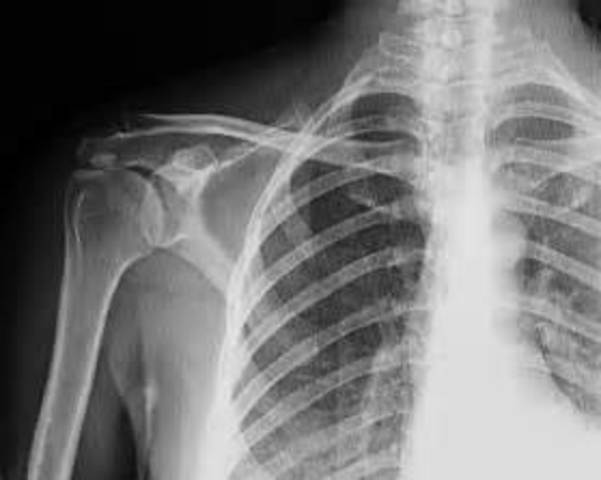

• Radiografia

Radiografia

El descubrimiento de los rayos X por el físico alemán Wilhelm Roentgen hizo posible que los anatomistas estudiaran los tejidos y los sistemas de los órganos en los seres vivos. La primera radiografía, tomada en 1896, fue de una mano humana.